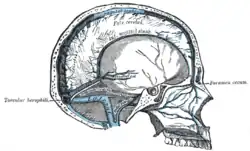

Твёрдая мозговая оболочка и её отростки

Твёрдая мозговая оболочка и её отростки Синусы основания черепа